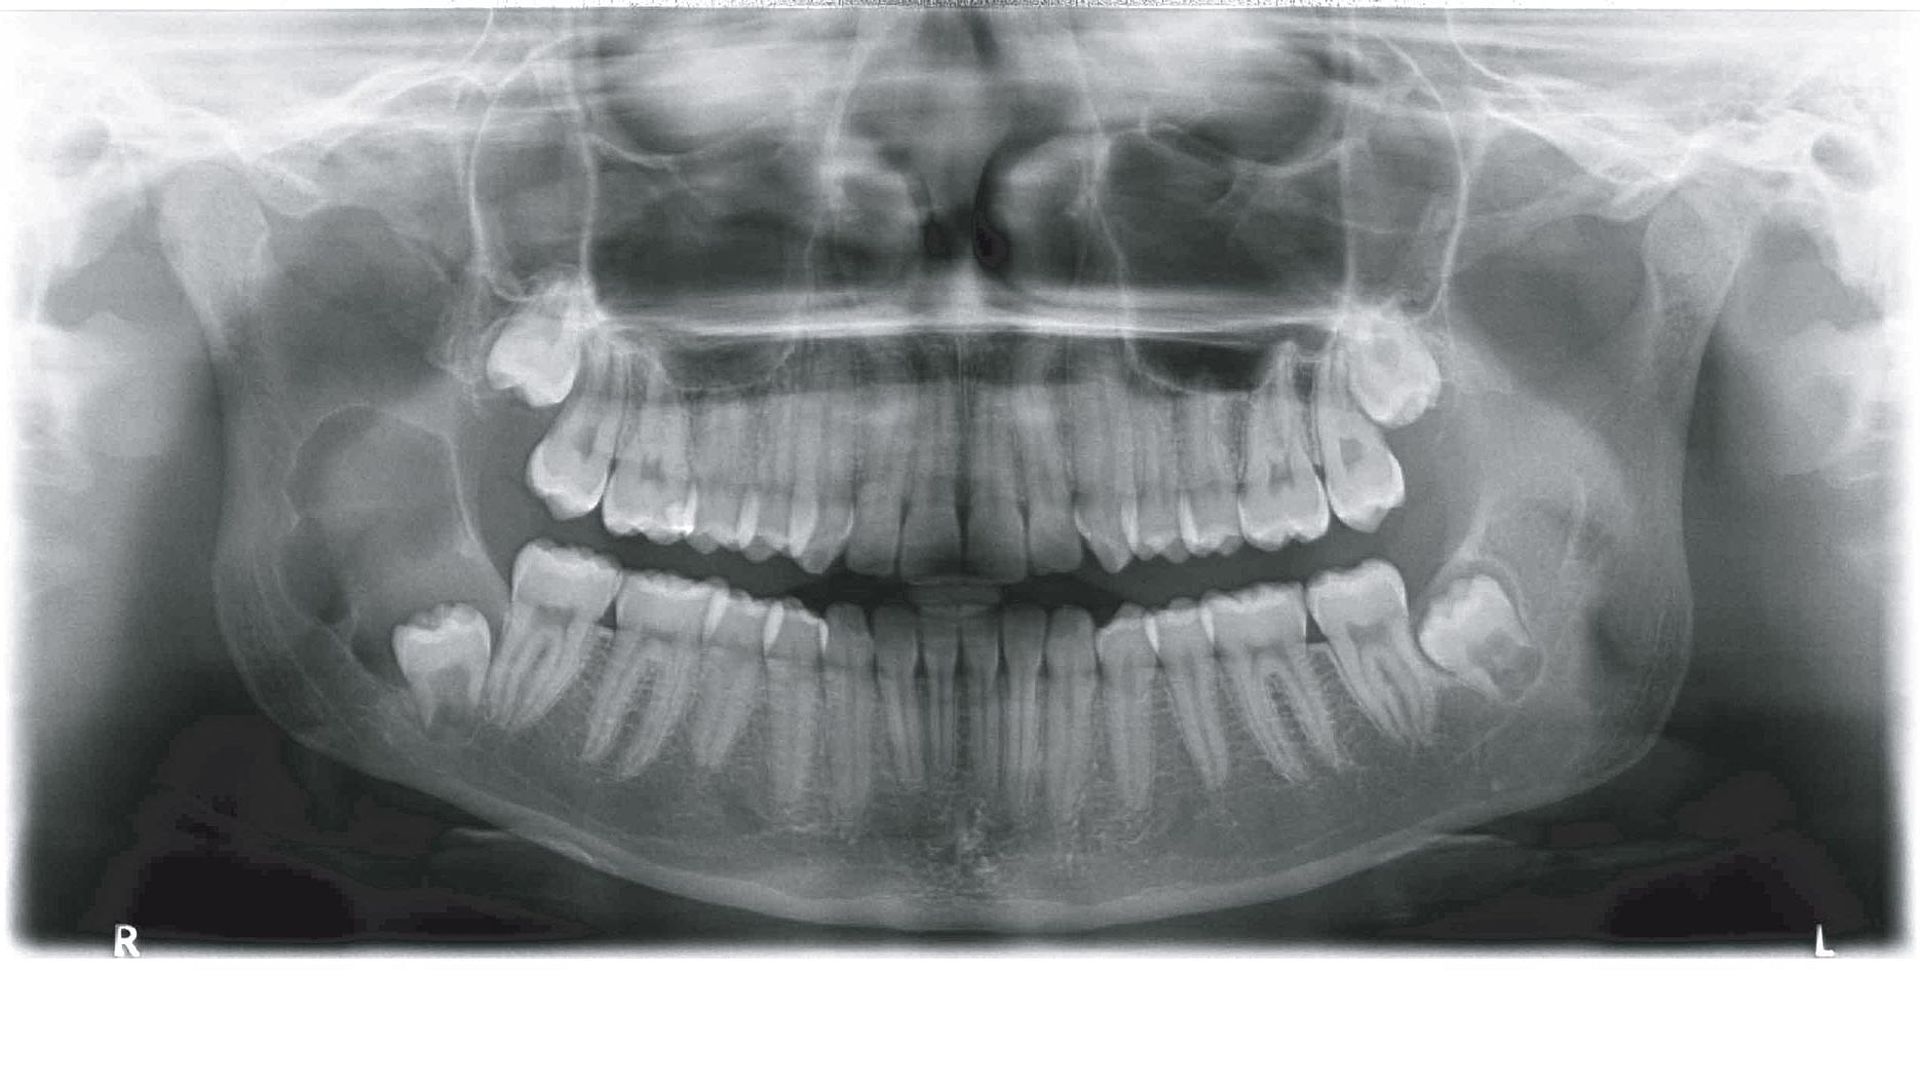

Röntgendiagnostik

Operationen an Zähnen und Kieferknochen sind ohne eine adäquate Röntgendiagnostik nicht möglich. Als Standardverfahren hat sich die Panoramaschichtaufnahme etabliert, die je nach Fragestellung durch intraorale kleine Zahnfilme ergänzt wird. Beide Techniken erfolgen in unserer Praxis digital und damit mit reduzierter Strahlenbelastung für den Patienten. Die Panoramaschichtaufnahme gibt einen hervorragenden Überblick über alle relevanten anatomischen Strukturen, die bei einer Operation berücksichtigt werden müssen. In einigen Fällen kann eine zusätzliche 3D-Aufnahme (DVT) vor der Behandlung sinnvoll sein, insbesondere zur Risikoabschätzung eines operativen Eingriffs, bspw. der Gefahr einer Nervenverletzung bei der Entfernung komplex verlagerter Weisheitszähne, zur Bestimmung der Größenausdehnung von Kieferzysten und -tumoren sowie bei komplizierteren Operationen an der Kieferhöhle.